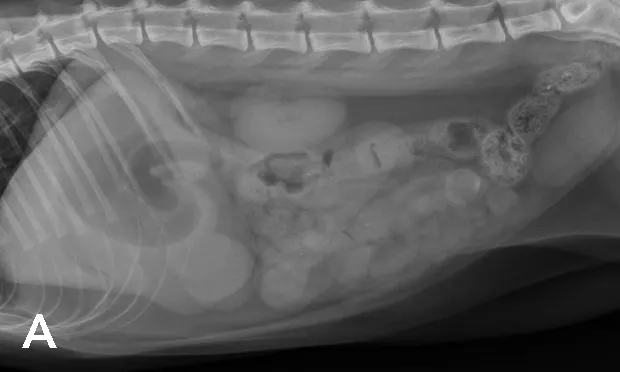

A) Right radiograph, B) Left radiograph, and C) Ventrodorsal radiograph

Radiographic Findings: The stomach (St) and duodenum (D) are severely distended with fluid and gas, suggesting intestinal obstruction or possibly pancreatitis with secondary ileus.

There is a 1.5-cm rounded opaque structure (arrows) in the caudal abdomen, to the left of the descending colon on the VD view. It is partially obscured by feces in the colon (C) on the left lateral view. The remaining organs and serosal detail appear normal.

Comments: We often perform left and right lateral radiographic views of the abdomen in cases of suspected GI foreign bodies and obstructions since the fluid and gas disperse into different portions of the GI tract. For example, any gas in the stomach rises to the pylorus (P) in left lateral recumbency and may outline a foreign body anchored to this region; this is particularly useful in suspected linear foreign bodies, which typically anchor to the tongue or pylorus and subsequently plicate varying degrees of small intestine.